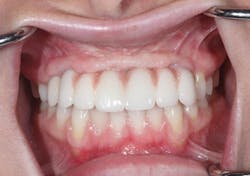

Final crowns were seated with Durelon (3M Oral Care) cement. Lingual access holes were sealed with flowable resin and cured (figure 15). No adjustments to the final restorations were needed. The patient was sent home with a final fixed crown and bridge (figures 16 and 17).

Figure 15: Final crown and bridges delivered

Figure 16: Day of delivery